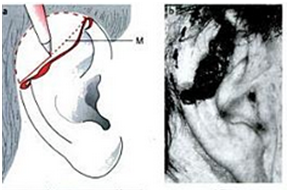

The first stage operation was implantation of the cartilage framework. The skin incised about 3-4 mm lower than the marked height of the stump.7,8 Subcutaneous pocket is developed, about 1 cm larger than the height of the superior helical margin and the post auricular stump skin is sutured to the lower margin of the incision. The framework is attached using 5.0 braided suture and inserted to the pocket. Closure of the skin wound, vacuum drainage, and mattress sutures (Figures 7-10).7

Figure 7 Marking and inscision.7